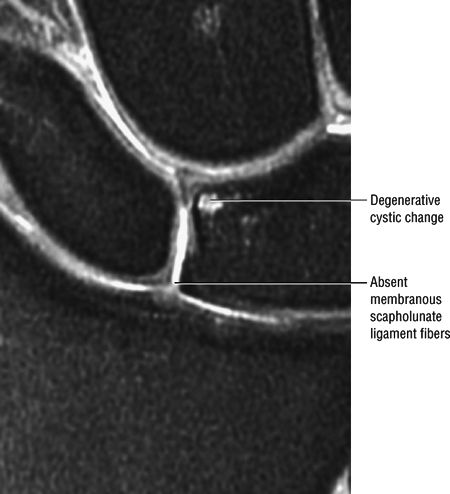

A perforation, identified by communication of fluid across a focal discontinuity, constitutes a communicating defect or tear. Small membranous perforations may exist in the presence of intact dorsal and volar portions of the scapholunate ligament. In fact, most degenerative perforations occur in the thin membranous portion of the scapholunate ligament, which is not thought to be biomechanically significant.59,60

Degenerative perforations in the membranous portion with intact volar and dorsal components (Fig. 10.99)